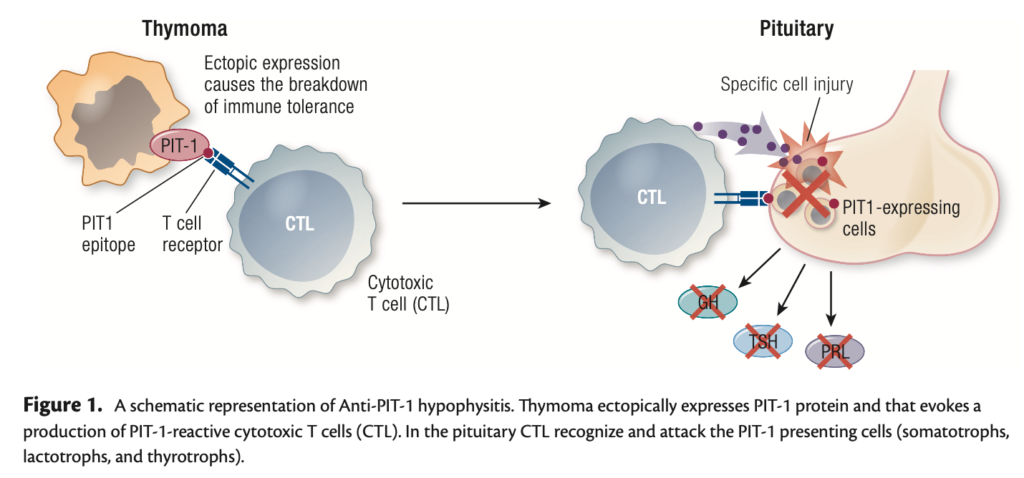

胸腺腫瘍細胞において本来存在していないPIT-1(GH,TSH,PRLの産生に必要な転写因子)が異所性に発現することで免疫寛容破綻が生じ、PIT-1を特異的に攻撃する細胞障害性T細胞が産生され、下垂体GH,TSH,PRL産生細胞を特異的に障害すると考えられている。PIT-1に対する自己抗体が認められる。

その後悪性リンパ腫、原発不明の肝転移症例においても抗PIT-1下垂体炎の症例の報告が同グループからあり、胸腺腫に特異的な疾患ではない下垂体自己免疫疾患・傍腫瘍症候群と考えられている。

機序